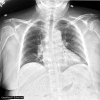

Lung ultrasound (LUS) is a dynamic, real-time, non-invasive bedside tool that offers increased sensitivity over standard imaging modalities in identifying pulmonary edema. This case highlights acute post-operative hypoxia secondary to pulmonary edema that was initially missed by chest radiography (CXR) and chest computed tomography (CT). The edema was diagnosed first on same day by bedside LUS, later seen on next day follow-up CXR and resolved with diuresis. LUS has demonstrated superior accuracy compared to CXR, but scant evidence compares it to CT. This case presentation serves to increase awareness of LUS as a highly sensitive and easy-to-use diagnostic tool for hospital providers in the evaluation of acute hypoxia.